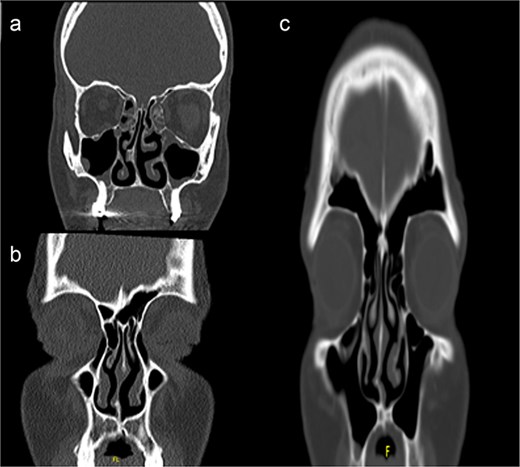

Our INES technique is specifically indicated for selected unilateral septum deviation. The procedure is particularly suitable for unilateral deviations with associated septal spurs, corresponding to Mladina type 5 and 6 deviations that affect the nasal patency (Fig. 1).

Computed tomography scans showing unilateral nasal obstruction caused by septal spurs, corresponding to Mladina type 5 (lateral nasal wall contact) and type 6 (bilateral spurs) nasal septum deviations.